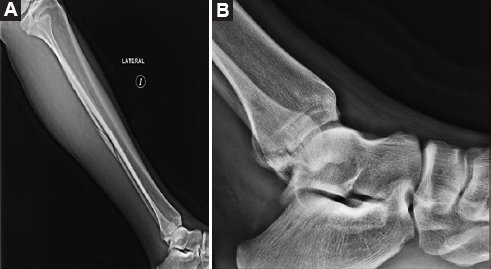

Varón de 49 años, sano, quien se ejercitaba regularmente con carreras y ciclismo seis veces por semana, y sin antecedentes de consumo de tabaco o alcohol, que acudió al servicio de urgencias después de sufrir una caída de bicicleta con traumatismo directo en su tobillo izquierdo. Experimentó un chasquido en el tobillo y no pudo identificar un mecanismo específico de lesión. Durante la evaluación inicial se constató incapacidad para la bipedestación, edema, limitación en los arcos de movimiento del tobillo y dolor a la palpación en el tercio medio de la diáfisis del peroné. Las radiografías mostraron una fractura espiroidea en el tercio medio de la diáfisis del peroné con desplazamiento posterior del tercer fragmento y una fractura de maléolo posteromedial desplazada (Fig. 1). Inicialmente se colocó una férula suropodálica posterior y se solicitó resonancia magnética de tobillo, en la cual se observaron fractura del maléolo posteromedial, ruptura del ligamento peroneoastragalino anterior, lesión condral en el margen medial del astrágalo con edema subcortical y ruptura de los fascículos profundos del complejo deltoideo (Fig. 2).

Figura 1. Radiografías iniciales. A: lateral de pierna izquierda en la que se observa una fractura espiroidea en el tercio medio de la diáfisis del peroné con desplazamiento posterior del tercer fragmento. B: lateral de tobillo izquierdo que muestra una fractura de maléolo posterior desplazada.